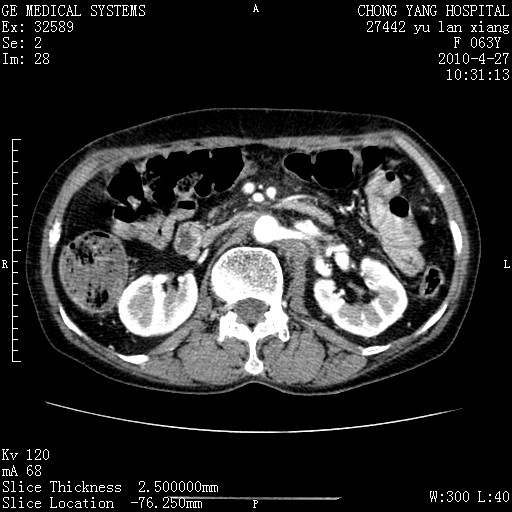

标题: CT26066:F63Y 上腹正中压痛半月,CA199:7400u/ml,MR示胰腺炎伴 [打印本页]

胰腺癌侵犯腹腔动脉干-分支、胃壁、左侧膈肌伴胰周及腹膜后淋巴结转移、胆囊切除术后。

胰腺癌侵犯腹腔动脉干-分支、胃壁、左侧膈肌伴胰周及腹膜后淋巴结转移、胆囊未显影。